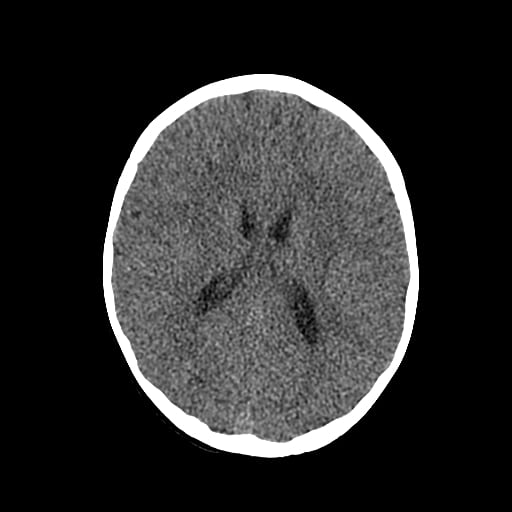

Age: 1

Sex: Male

Indication: Fall